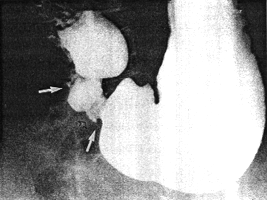

Case 29.1 C.W., 60 year old male, presented with intermittent epigastric pain and malaena. Radiographic examination showed a gastric ulcer, 2.5 cm in diameter, in the posterior wall of the upper corpus, approximately 10 cm proximal to the pylorus; the features were those of a benign ulcer. There was constant contraction (or spasticity) of the pyloric sphincteric cylinder, the contracted region being 3.0 to 4.0 cm in length (Fig. 29.1). Cyclical contraction and relaxation of the cylinder, normally occurring at a rate of 3 cylces per minute, was absent; the contraction of the cylinder "fixed" the pyloric aperture in the open or patent position. Mucosal folds in the contracted cylinder appeared normal, but their movements were restricted. A shallow, concave identation of the base of the duodenal bulb, caused by the pyloric ring, was evident. Peristaltic waves in the remainder of the stomach were normal; emptying of liquid barium appeared normal. Two weeks later a Billroth I partial gastrectomy confirmed the large, chronic gastric ulcer. No macroscopic abnormality was seen or felt in the pyloric region. Histology of the ulcer proved it to be benign; microscopic examination of the pyloric region was not carried out.

| Fig. 29.1 A-D. Case C.W. Constant contraction or spasticity of pyloric sphincteric cylinder. Cyclical activity absent. Pyloric aperture "fixed" in patent position (B-D) | |